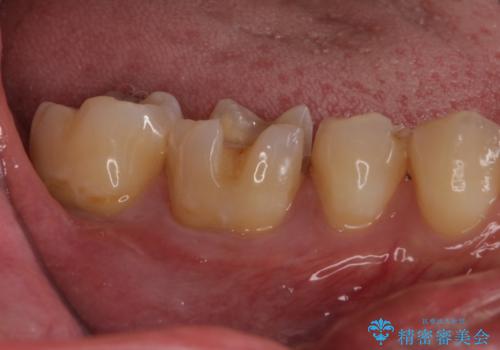

- 他院で行った、古いセラミックが欠けたとのことでご来院された患者様です。

古いセラミックを外すと、無数のヒビが入っており、そこからできた新しい虫歯がありました。

古い材料も虫歯もすべて除去して、根本からやりかえました。

セラミックが欠けるほど強い力がかかっているということは、ご自身の歯も割れている(小さいヒビ等も含む)可能性があります。拡大鏡でしっかり見ながら治療します。